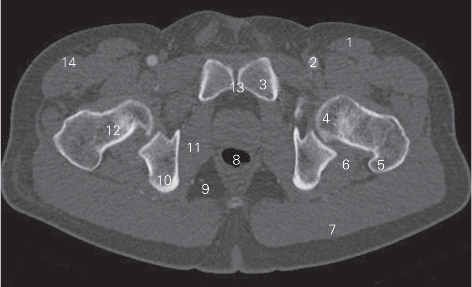

图5-3 经股骨颈的横断层CT图像(骨窗)

1 缝匠肌 sartorius 2 股动脉 femoral artery

3 耻骨上支 superior ramus of pubis 4 股骨头 head of femur

5 大转子 greater trochanter 6 股方肌 quadratus femoris

7 臀大肌 gluteus maximus 8 肛管 anal canal

9 坐骨肛门窝 ischioanal fossa 10 坐骨体 body of ischium

11 闭孔内肌 obturator internus 12 股骨颈 neck of femur

13 耻骨联合 pubic symphysis 14 阔筋膜张肌 tensor fasciae latae